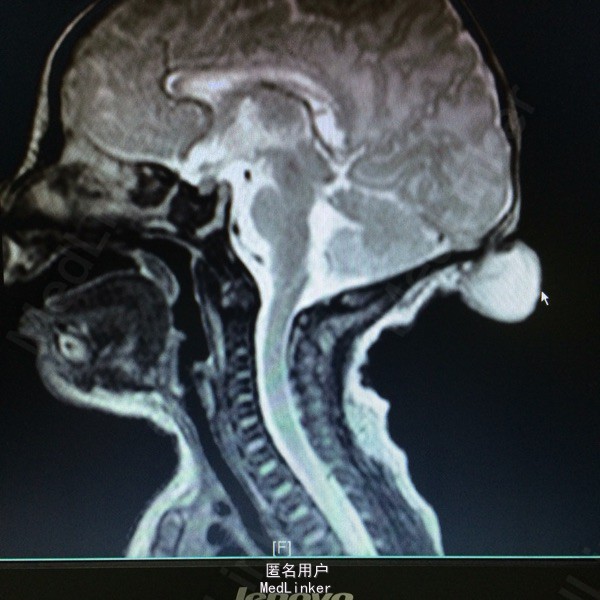

主诉:发现枕部包块1月余 病史:患儿2月大,第3胎第3产,经剖宫产,查体发现枕后部有一圆形肿物突出,约等3*3大小,透光实验阳性,质软。

查体:神志清醒,枕后部可见一圆形肿物突出,约3*3cm大小。质软,表面无溃疡等 辅助检查:胸片提示新生儿羊水吸入综合症,头颅MR提示局部脑脊膜膨出

诊断:后枕部脑脊膜膨出 处理:行脑脊膜膨出修补术,病理提示符合脑脊膜膨出